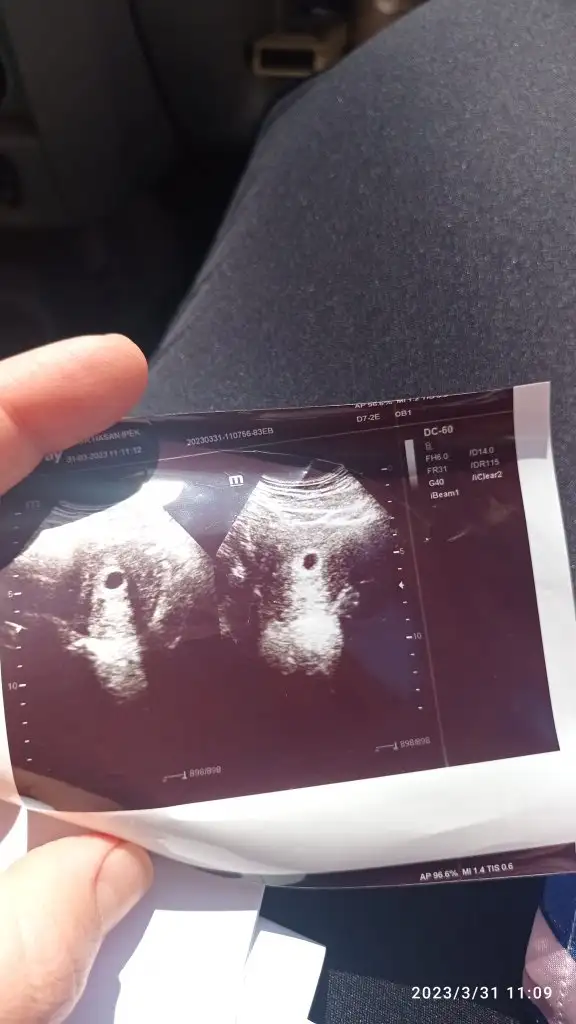

keseye göre tahmin yapan birileri vardıııı 7+5

Eklentiler

• 06169376-19D5-486F-8187-FAE3BEFBABD4.webp

06169376-19D5-486F-8187-FAE3BEFBABD4.webp

26,6 KB · Görüntüleme: 81